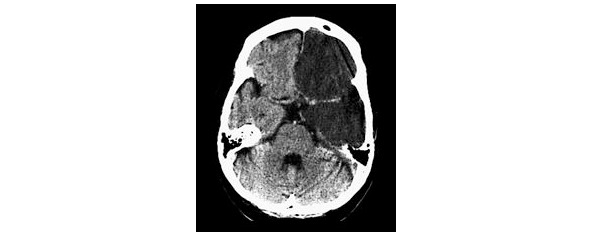

Ишемический инсульт обусловлен нарушением проходимости мозговых сосудов вследствие закупорки их атеросклеротической бляшкой, эмболом, тромбом или в результате спазма сосудов мозга различной локализации (рис. 1).

Такой инсульт может возникнуть при атеросклерозе сосудов мозга, по типу кардиогенной тромбоэмболии, понижении АД и по другим причинам.

Среди гетерогенных подтипов ишемического инсульта выделяют: атеротромботический вариант, кардиоэмболический, лакунарный, гемодинамический, гемореологический (рис. 2).

Среди геморрагических вариантов ОНМК выделяют: паренхиматозное кровоизлияние, вентрикулярное кровоизлияние, паренхиматозно-вентрикулярное кровоизлияние (рис. 3), а также субарахноидальное кровоизлияние.